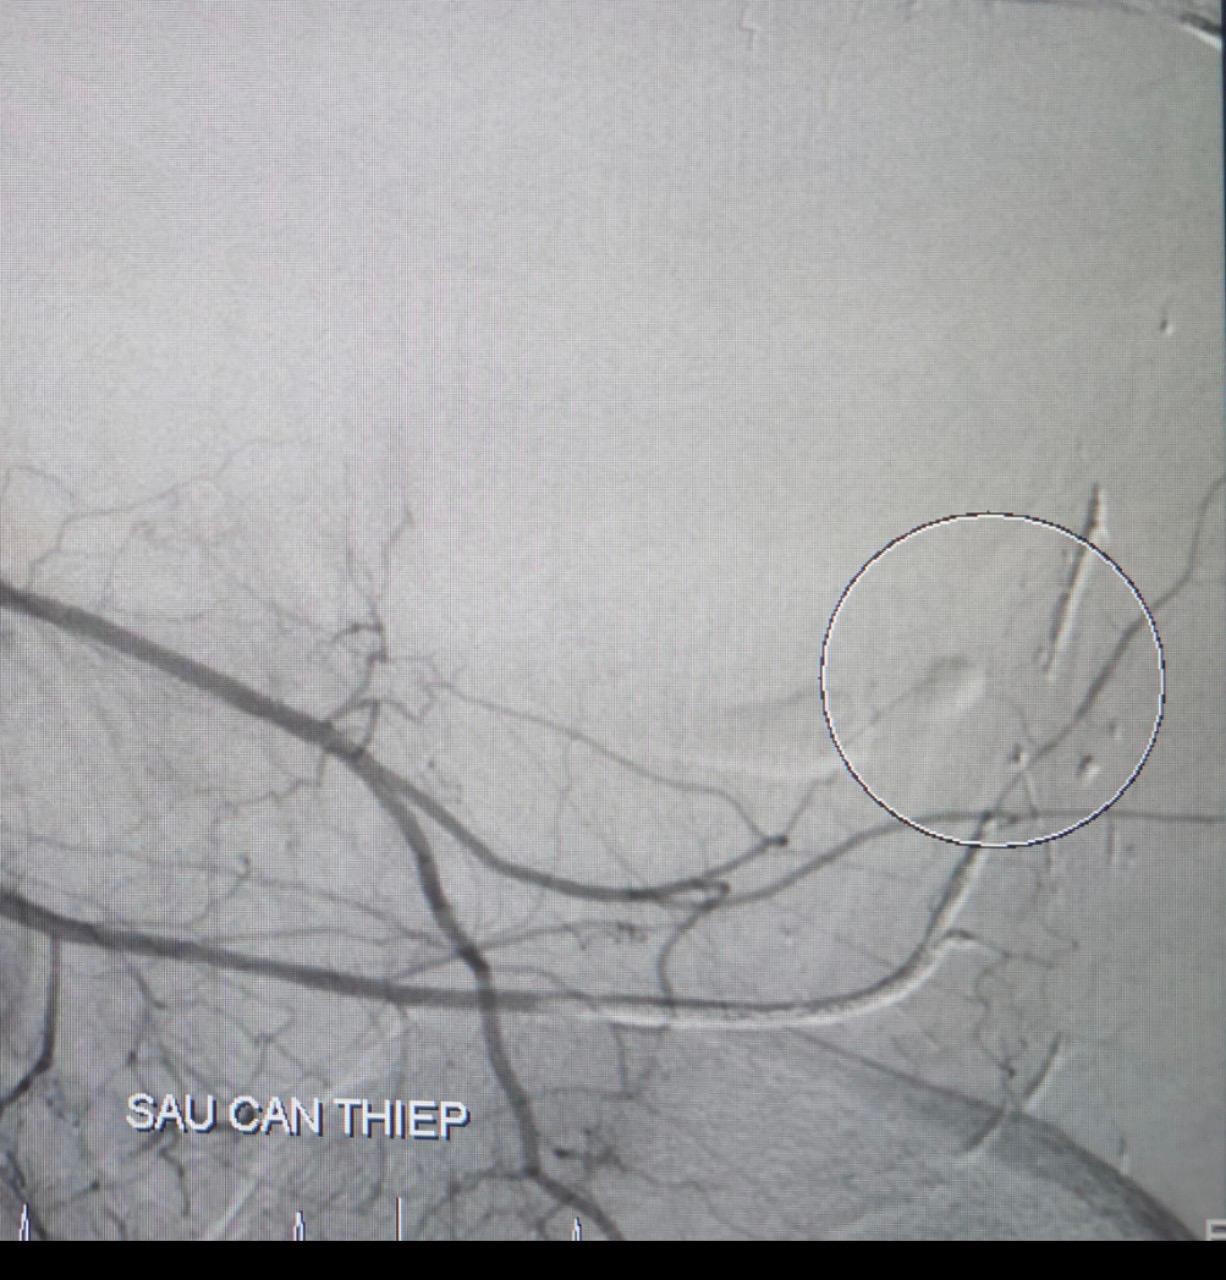

![]() |

Hình ảnh sau can thiệp , không thấy ổ xuất huyết |

Bệnh nhân có chỉ định chụp và nút động mạch cầm máu các tạng số hóa xóa nền. Kết quả ghi nhận đa ổ xuất huyết xuất phát từ nhánh động mạch chậu trong trái, tiến hành bơm hỗn hợp keo.

Tình trạng bệnh nhân sau can thiệp huyết động ổn được tiếp tục theo dõi tại khoa Hồi sức tích cực – Chống độc. Tuy nhiên, sau đó bệnh nhân bị xuất huyết nội mạch tái phát, rối loạn đông máu và được can thiệp nội mạch cấp cứu lần 2.